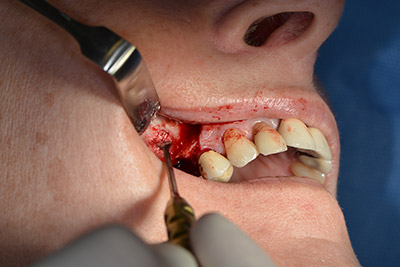

Im nächsten Schritt wird die Sinusbodenelevation mit simultaner Implantation durchgeführt. Für die bukkale Fensterung der Kieferhöhlenwand gibt es auch hier bei der Implantmed an der ersten Position eine Voreinstellung.

Mit 35.000/min wird das Fenster angelegt und anschließend die Schneidersche Membran nach kranial präpariert. (Abb. 13 bis 14).

Präparieren der Schneiderschen Membran

Abb. 13